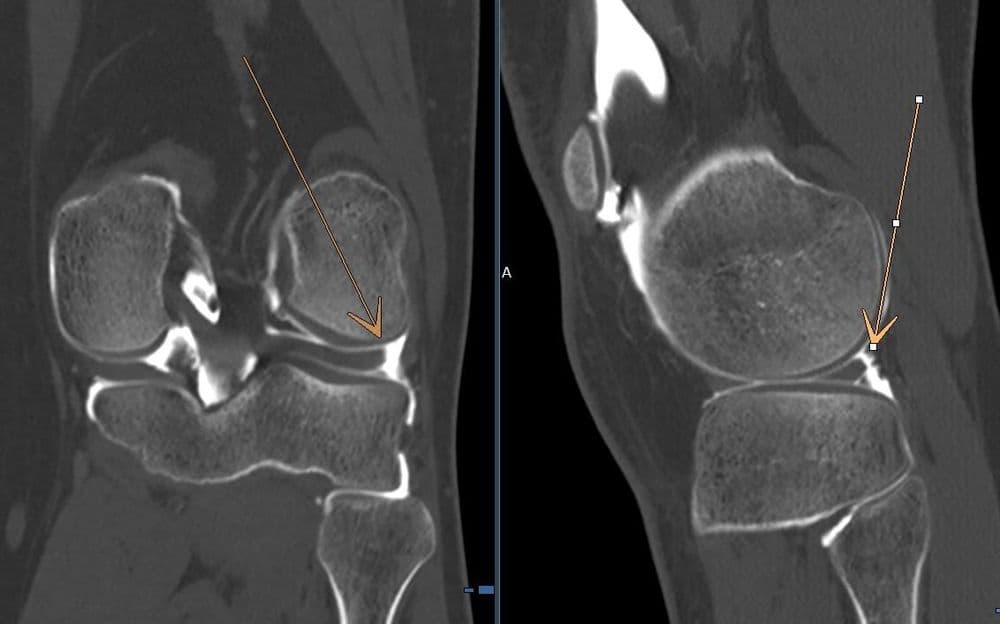

Apport de l'arthroscanner dans la recherche de fissure méniscale en complément de l'IRM

MRICT

CT